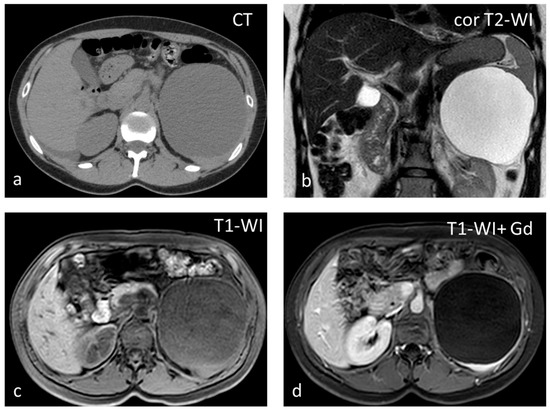

Inflammatory myofibroblastic tumor (IMT), formerly known as inflammatory pseudotumor, is an uncommon benign splenic lesion. It has been described in virtually all major organs with a few exceptions. In the liver and spleen, inflammatory pseudotumor is possibly linked to Epstein–Barr infection [13]. The prevalence is similar in both sexes, with a peak incidence in middle age. The lesions reported are usually large, measuring > 10 cm. It is composed of a combination of inflammatory and myofibroblastic spindle cells. Usually an incidental finding, it is included in the differential diagnosis of malignant splenic lesions, although currently, the World Health Organization classification of soft tissue tumors places IMTs in an intermediate category between benign and malignant, with metastases in less than 5% of extrasplenic cases [14,15]. In the US, inflammatory myofibroblastic tumors appear as solid hypoechoic masses. CT shows hypoattenuating hypoenhancing lesions, and stellate central calcifications seen on CT scans make the diagnosis very likely [16]. They present as hypointense masses both on T1-WI and T2-WI, with slow delayed enhancement (Figure 1) [17]. The diagnosis can be confirmed reliably only by histopathological and immunohistochemical evaluations. Although recurrence and metastatization have not been described for splenic inflammatory myofibroblastic tumors, patients must be followed up as these are considered tumors with intermediate malignant potential [14,17].

Figure 1.

Large solid lesion, in keeping with an inflammatory myofibroblastic tumor, slightly hypodense in the non-contrast CT scan (a), depicting slightly heterogenous/patchy gradual enhancement pattern post-contrast enhancement (b,c). The lesion appears iso– to hypointense on T2-weighted MRI, more conspicuous than in the non-contrast CT scan (d).